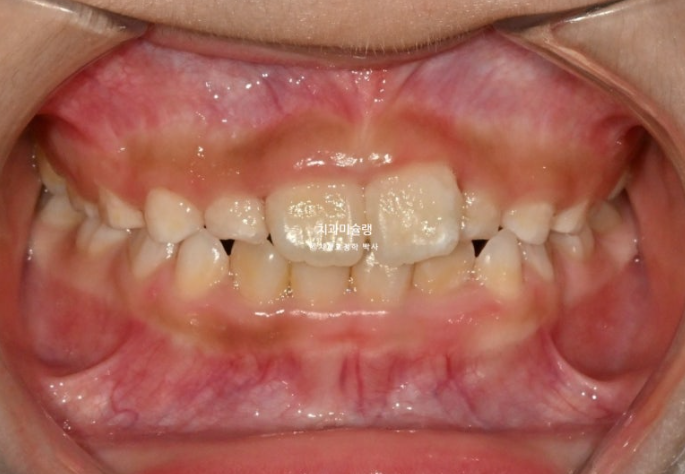

앞니가 거꾸로 물려서 온 7세 어린이 입니다.

윗니가 전체적으로 아랫니와 거꾸로 물리는 반대교합 입니다.

공간부족으로 앞니가 덧니처럼 나왔습니다.

엑스레이 골격분석 결과 뼈의 주걱턱은 아니였어서 프리올소 치료를 권유드렷고